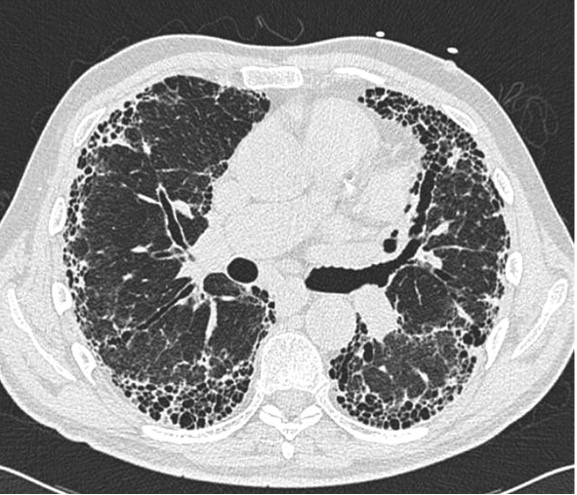

A 71-year-old man presents with complaints of a dry cough and progressive dyspnea on exertion for the past year. He is a former cigarette smoker with an 18 pack-year history. His respiratory symptoms worsened after having a SARS-CoV-2 infection approximately 6 months ago, for which she was treated as an outpatient with a 5-day course of nirmatrelvir/ritonavir (Paxlovid). He unfortunately developed “rebound COVID” though clinically asymptomatic at this time. He has a history of hypertension that is well controlled on hydrochlorothiazide (HCTZ). His family history is notable for his mother who died from “pulmonary fibrosis.” Review of systems is otherwise unremarkable with no occupational or environmental exposures. Physical examination is normal except for bibasilar crackles noted on lung examination. Comprehensive lab testing including an antinuclear antibody and rheumatoid factor are unremarkable. Pulmonary function testing shows a TLC 70%, FVC 70%, FEV1 75%, FEV1/FVC 84% and DLCO 70%. A high-resolution CT chest is performed with 2 images shown.

This patient has idiopathic pulmonary fibrosis (IPF) on the basis of the chest CT imaging showing a typical usual interstitial pneumonia (UIP) pattern of peripheral, basilar-predominant reticulation with traction bronchiectasis and honeycombing fibrosis and the negative work-up for underlying causes of pulmonary fibrosis. In order to diagnose IPF, a comprehensive evaluation for any relevant secondary causes for pulmonary fibrosis such as medications, pets, home, or work exposures to suggest hypersensitivity pneumonitis or occupational lung disease must be done. Also, rheumatologic diseases such as rheumatoid arthritis, scleroderma or SLE must also be evaluated if clinically indicated based of the history, physical exam or laboratory results. Bronchoscopy with biopsy or surgical lung biopsy is unnecessary for diagnosis in this case given the classic CT chest findings and would only subject the patient to an increased risk of morbidity and mortality. Patients with IPF should be offered antifibrotic therapy with either nintedanib or pirfenidone, either of which has been demonstrated to slow the progression in the decline in FVC.